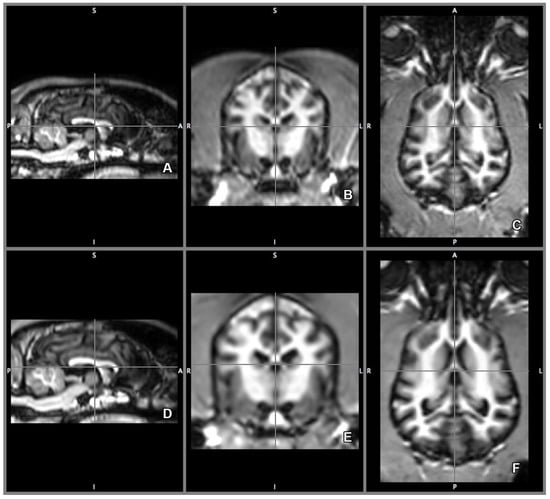

2.5. Morphology and Size of the Measured Brains

3. Results